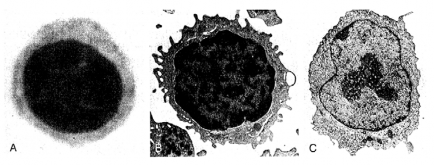

Hình 5.2. Hình thái học lymphô bào

A. Hình ảnh kính hiển vi quang học của lymphô bào trên tiêu bản máu ngoại vi

B. Hình ảnh kính hiển vi điện tử của tế bào lymphô nhỏ

C. Hình ảnh kính hiển vi điện tử của tế bào lymphô lớn (nguyên bào lymphô)